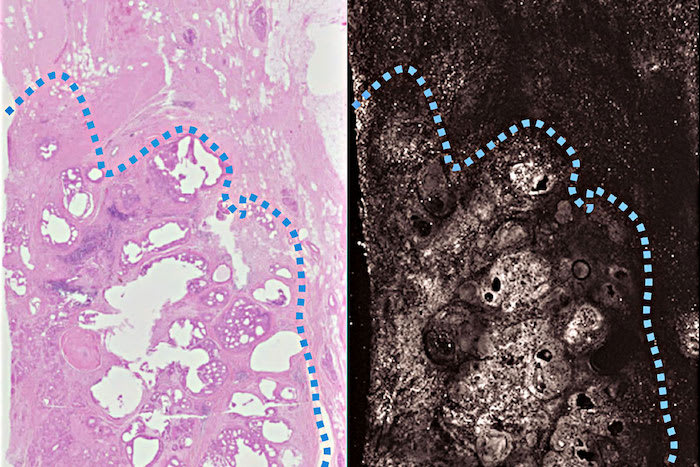

To speed up the process, the researchers took advantage of a phenomenon known as the photoacoustic effect. When a beam of light of the right wavelength hits a molecule, some of the energy is absorbed and then released as sound in the ultrasound range. These sound waves can be detected and used to create an image. The photoacoustic image matched the stained samples in all key features. The architecture of the tissue and subcellular detail such as the size of nuclei were clearly visible.